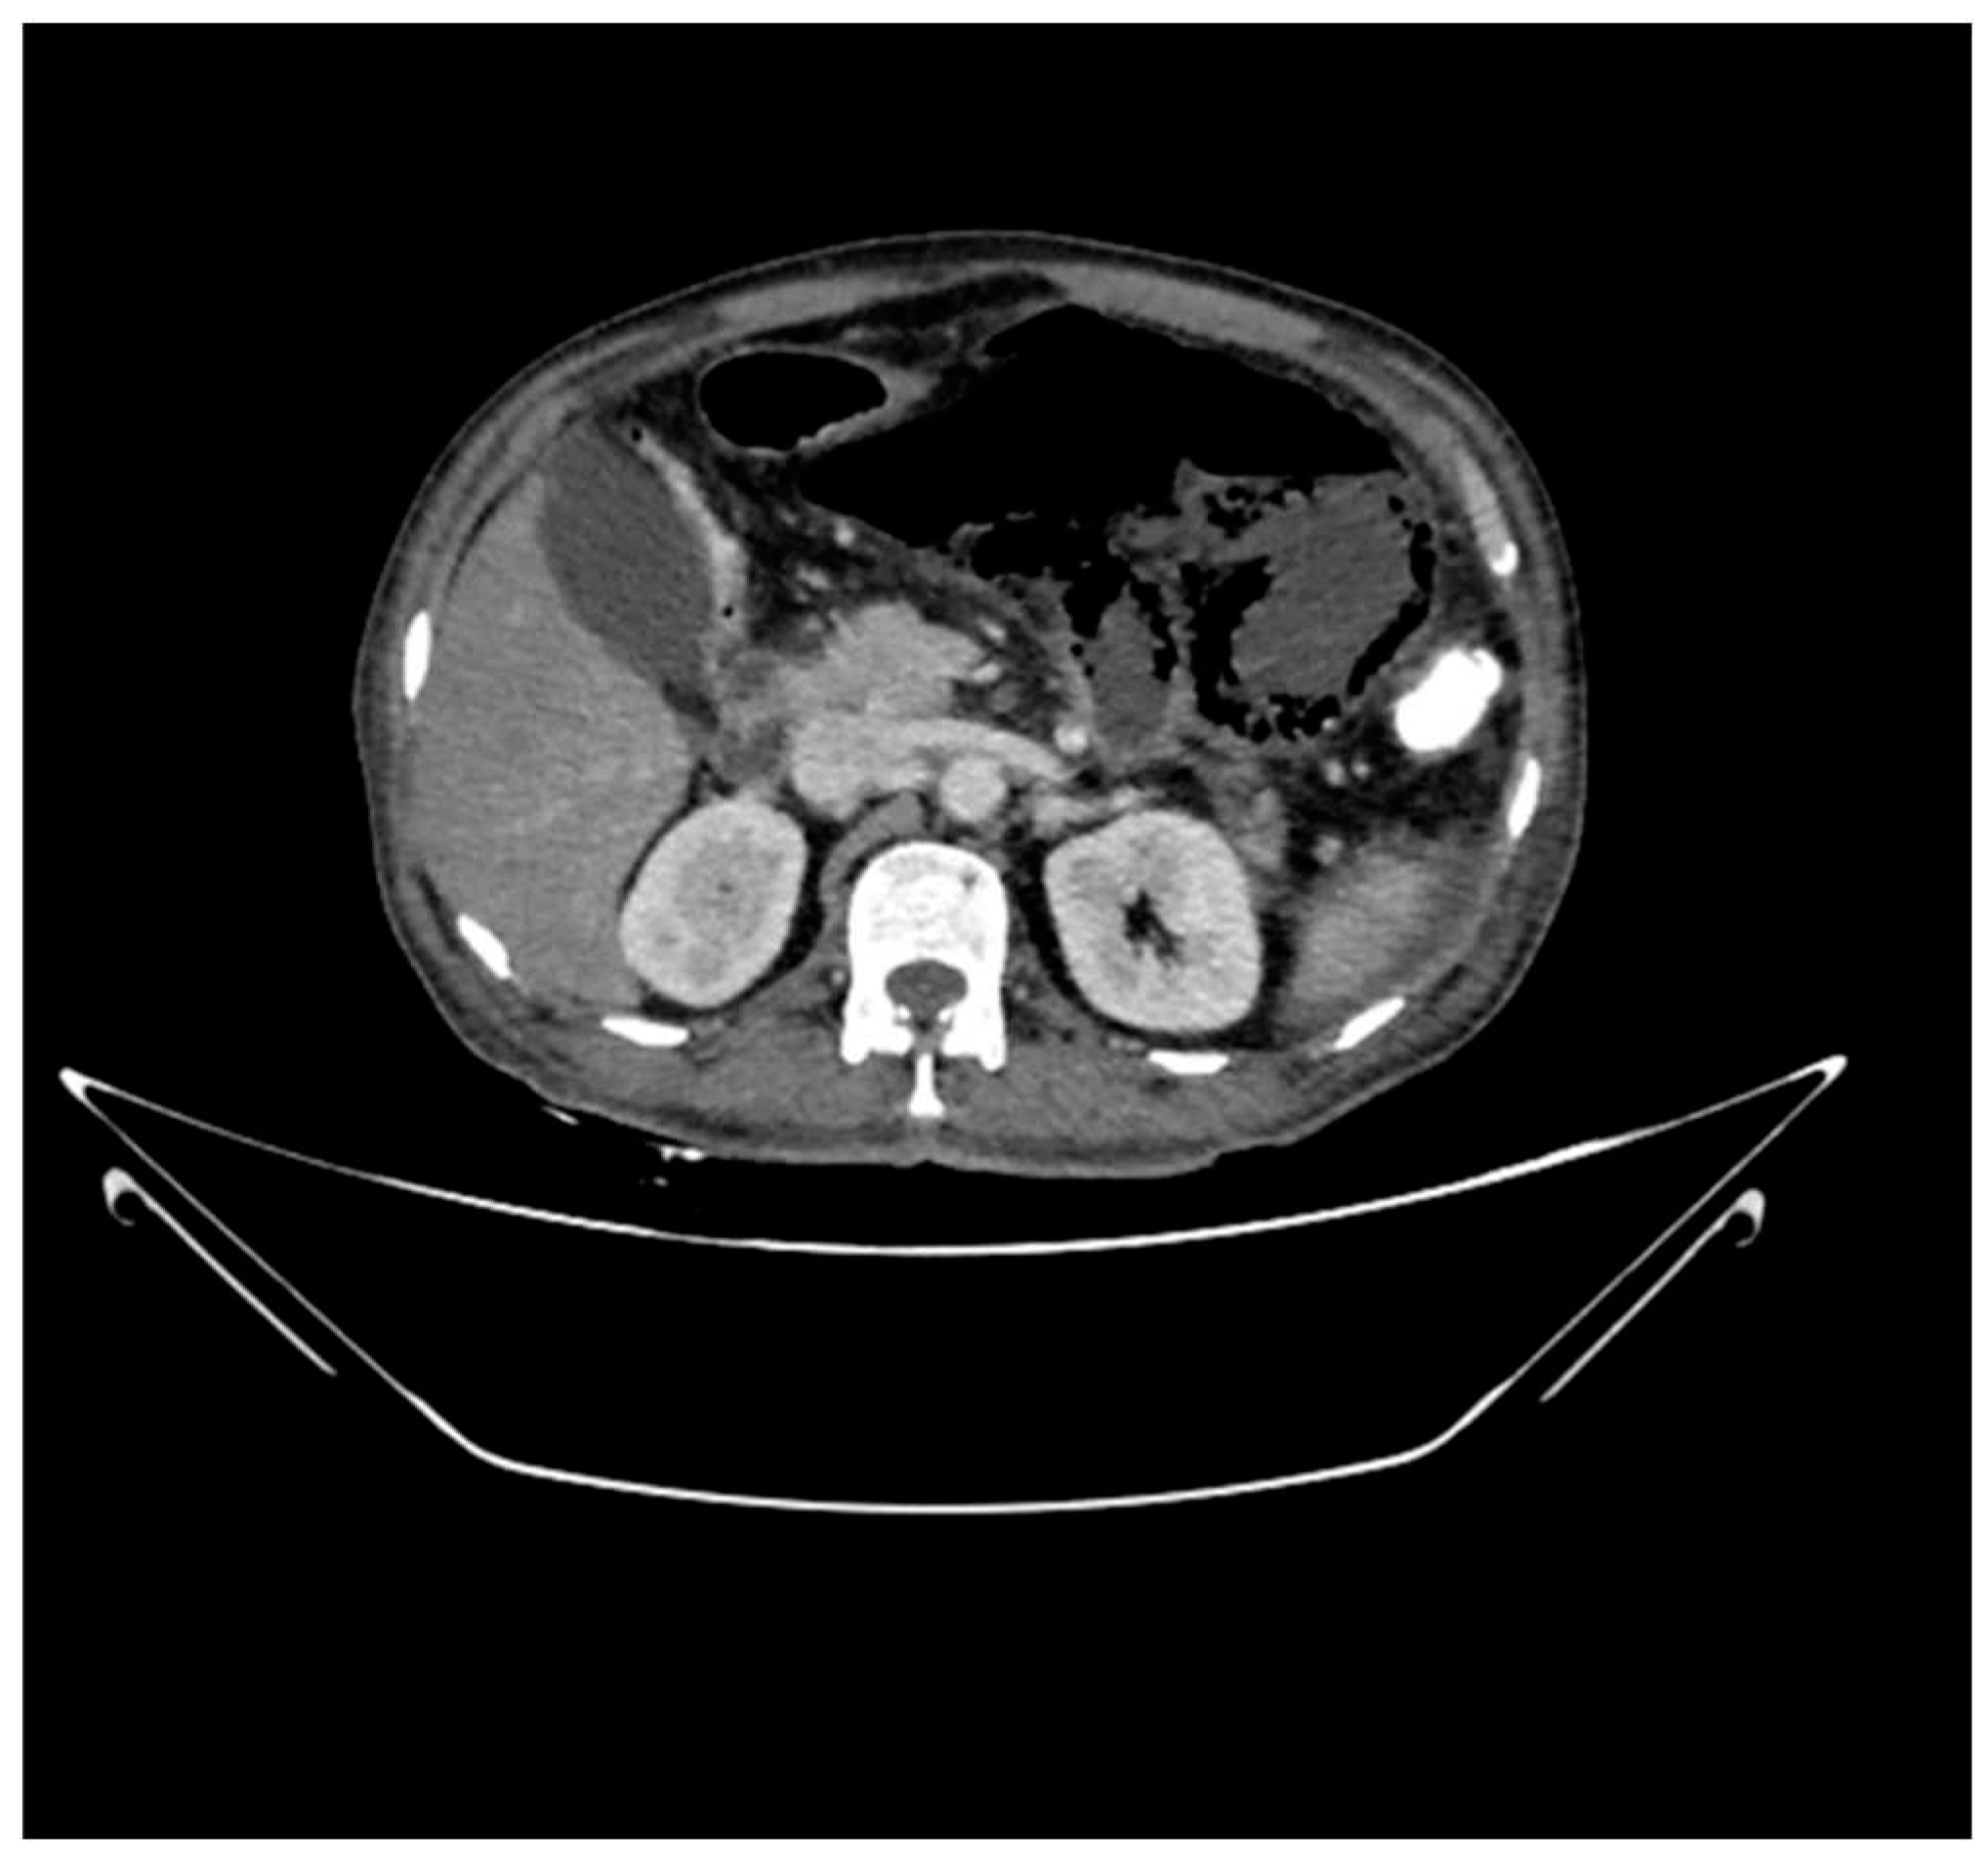

On MDCT imaging of the abdomen and pelvis with oral, per-rectal and IV contrast using 60 ml of non-ionic contrast showed circumferential air within the walls of proximal jejunal loops beyond the duodenal-jejunal junction Contiguous axial, coronal, and sagittal images were obtained. It gives the suggestive diagnosis of Pneumatosis intestinalis with a barely appreciable wall of the bowel in the left hypochondriac region. One of the loops appears dilated due to the presence of air within the walls with a maximum diameter of 6 cm. There is free fluid with fat adjacent to it. The gall bladder is distended with hyperdense sludge. A complete contrast filling defect is noted in the proximal superior mesenteric artery for a segment of 2.7 cm from its origin which distally appears patent.

Figure 1. Circumferential air within the walls of Jejunal loops.

Calcified atheromatous plaques are noted at the origin of the celiac trunk for a segment of 4 mm and at the origin of the inferior mesenteric artery for a segment of 5 mm from their origins respectively causing severe luminal narrowing which distally appears patent.

The above CT scan findings are suggestive of a few proximal jejunal loops beyond the duodeno-jejunal junction showing circumferential air within the wall giving evidence of Pneumatosis Intestinalis with barely appreciable wall. One of the loops appears air-filled and distended with surrounding fluid in the left hypochondriac region with evidence of proximal superior mesenteric artery thrombosis causing jejunal ischemia.